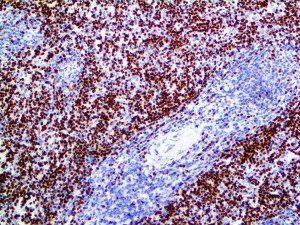

It is the ICU physician who is most likely to witness one of the deadliest manifestations of the abnormal immunological response, the cytokine storm syndrome (CSS). This response is also referred to by some as the cytokine release syndrome (CRS). CSS is characterized by continuous activation and expansion of macrophage and lymphocyte populations, which secrete large amounts of cytokines, causing the cytokine storm. This massive cytokine release is akin to hemophagocytic lymphohistiocytosis (HLH) disease, a syndrome characterized by initial unchecked and persistent activation of cytotoxic T lymphocytes and NK cells.

Clinical and laboratory manifestations of HLH include fever, enlarged liver and/or spleen, neurologic dysfunction, coagulopathy, liver dysfunction, cytopenias (i.e., low levels of erythrocytes, leukocytes, and/or platelets), hypertriglyceridemia, hyperferritinemia, hemophagocytosis, and eventually diminished NK cell activity as the immune system becomes progressively paralyzed. HLH can be familial (primary HLH) or secondary to another disease process (sHLH), such as rheumatic disease, in which it is referred to as macrophage activation syndrome (MAS, characterized by elevated ferritin).